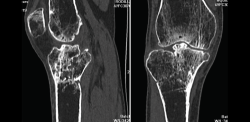

Numerosos estudios demuestran la utilidad de la RM para definir la estabilidad o inestabilidad de la lesión en la osteocondritis, destacando su carácter no invasivo y la capacidad de valorar la progresión y la respuesta al tratamiento(21)(Figuras 53 y 54).

Figura 54. Corte de secuencia T1 y T2 Fat-Sat coronal de resonancia magnética: gran osteocondritis en el cóndilo femoral interno con edema en la medular adyacente.